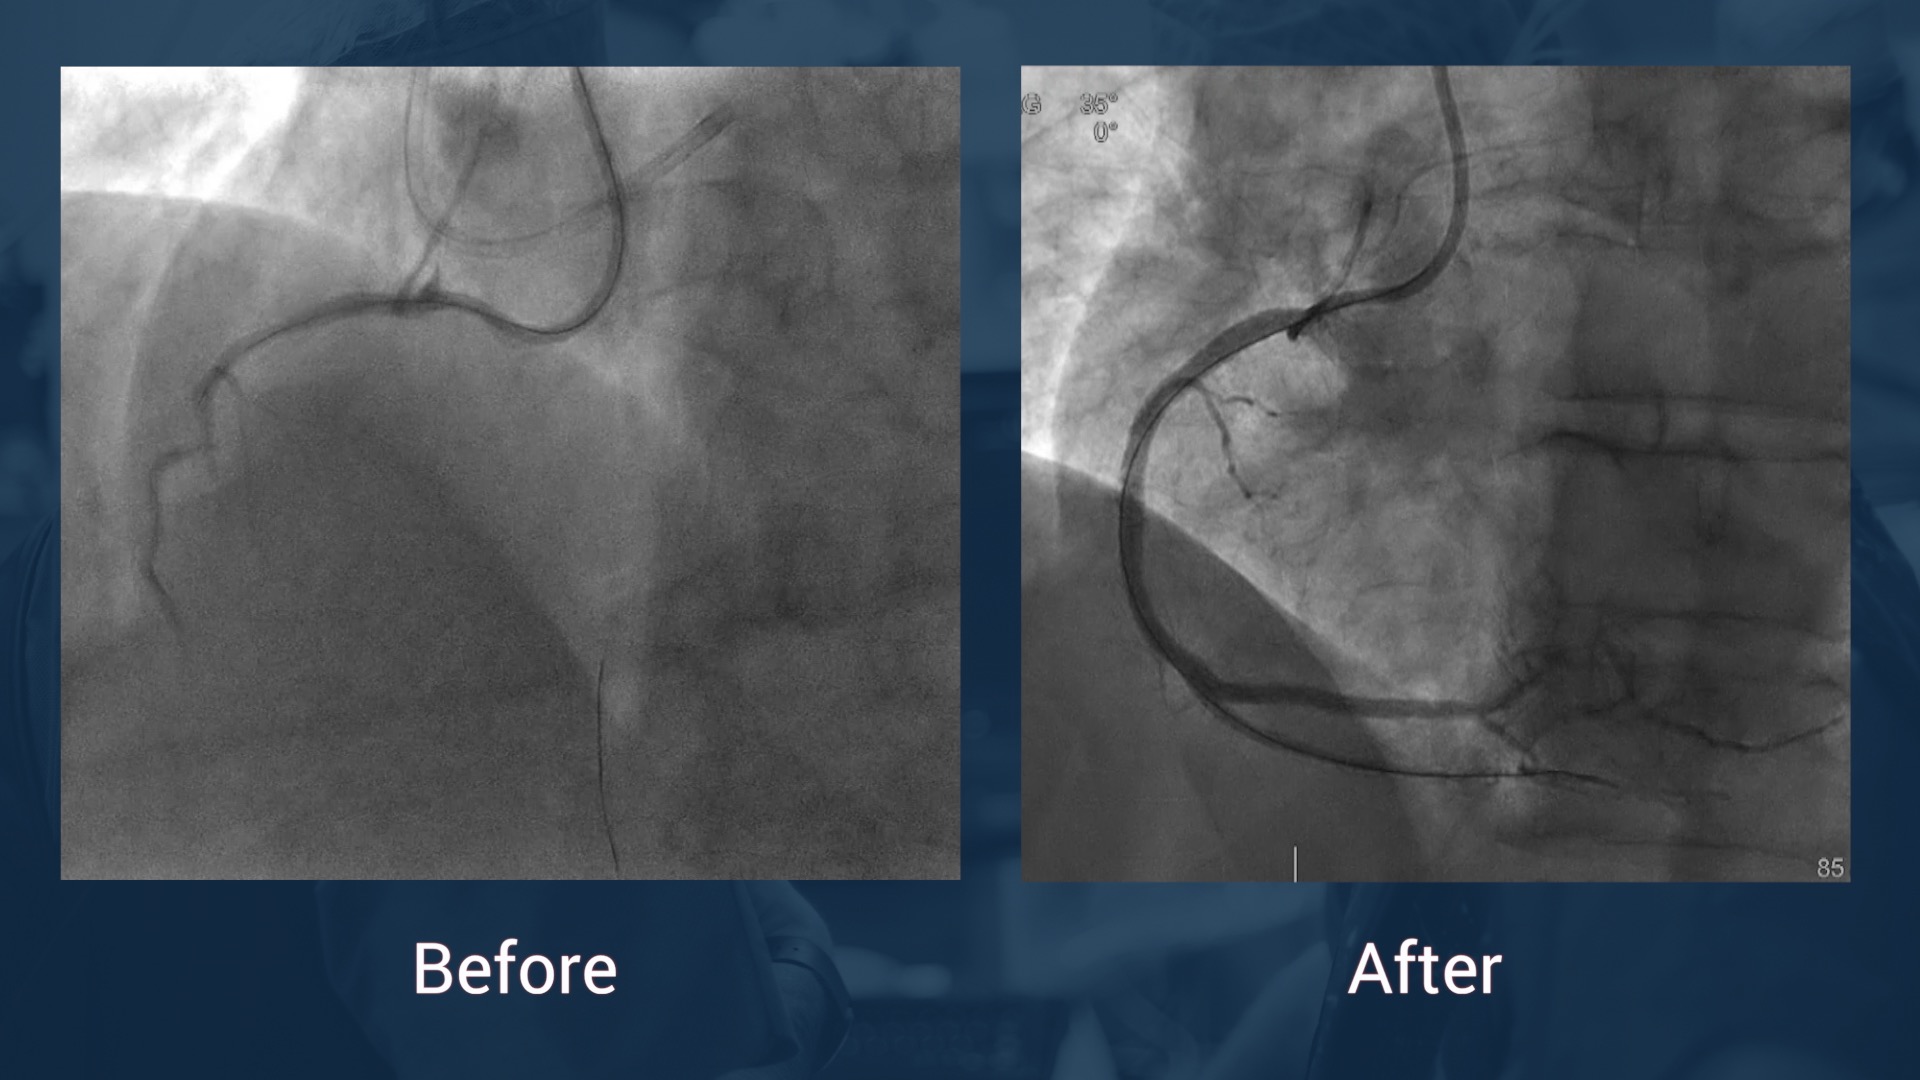

• Coro:  chronic total coronary occlusion of the right coronary artery,significant stenosis of the PDA, significant stenosis of the distal left main trunk ant of the proximal LAD